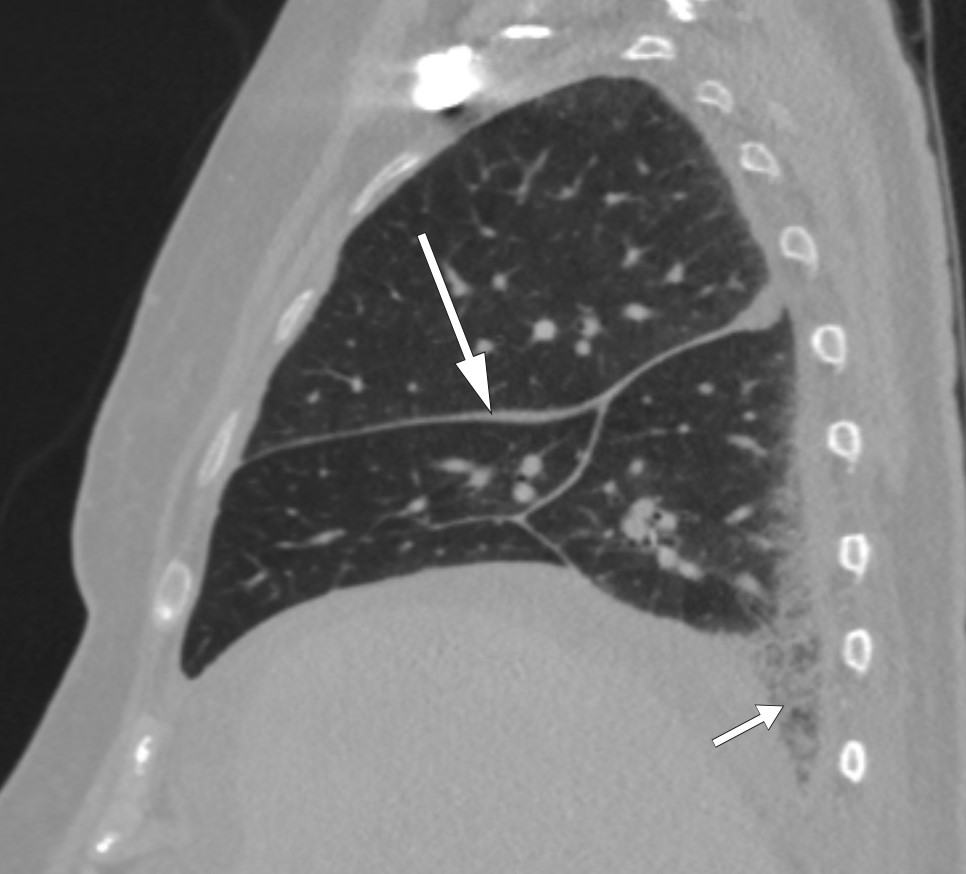

CT abdomen-bildene ble oversendt til et universitetssykehus for ny vurdering. Radiologen bemerket påfallende forandringer rundt nyrene (fig 1) – et funn som tydet på såkalte hårete nyrer (hairy kidneys). Pasienten ble overført til universitetssykehuset for videre utredning.

Hårete nyrer er uttrykk for retroperitoneal fibrose som infiltrerer perirenalt fettvev, med fortykkelse av nyrekapslene. Ved funn av retroperitoneal fibrose er den som regel lokalisert rundt abdominalaorta og iliaca communis-karene, men den kan også være mer utbredt (9). Retroperitoneal fibrose er i over 70 % av tilfellene idiopatisk (10), mens de resterende kan skyldes for eksempel medikamenter, malignitet, infeksjoner, kirurgi, stråling, amyloidose og histiocytoser (9). Idiopatisk retroperitoneal fibrose klassifiseres ofte som en kronisk periaortitt, enten isolert eller assosiert med andre autoimmune sykdommer eller immunglobulin G4 (IgG4)-relatert sykdom (11). Symptomene kan være vage og lite spesifikke. Det typiske er korsryggssmerter, eventuelt med utstråling til lysken, ledsaget av vekttap, redusert appetitt, utmattelse, feber, oppkast og kvalme. Ikke rent sjelden – som hos vår pasient – oppdages tilstanden tilfeldig når abdomen undersøkes radiologisk. Men i vårt tilfelle var infiltrasjonen mer utbredt enn det som er vanlig ved retroperitoneal fibrose.

I tillegg til de perinefriske forandringene var det påfallende funn på CT thorax (fig 2) og helkroppsscintigrafi (fig 3). Som et bifunn ble det også funnet en liten lungeembolus. MR hjerte og ekkokardiografi påviste lokalt fortykket perikard, mens MR caput og orbita viste normale funn. Abdominal paracentese viste CD68-positive og CD1a-negative makrofager og ingen tegn til mikrober. I ascitesvæsken, som var gjennomskinnelig og gul, var albuminnivået 13 g/l og proteinkonsentrasjonen 24 g/l (under 30 g/l tydet på transudat). Serum-ascites-albumin-gradienten (SAAG) var 9 g/l, forenlig med at årsaken til ascites ikke var portal hypertensjon. Leukocytter i ascitesvæsken var 0,20 · 109/l, noe som utelukket spontan bakteriell peritonitt. På blodutstryk var det granulocytose og trombocytose, mens benmargsutstryk viste reaktiv/normal benmarg. Benmargsbiopsi viste noen svakt reaktive megakaryocytter, og biopsier fra femur påviste kun osteomyelosklerose. Biopsi fra perinefrisk vev viste fibrose og histiocytter som var positive for CD68 og negative for CD1a, samt en uspesifikk reaksjon for S100-proteiner. Genetisk testing for BRAF-mutasjon var negativ.

Symmetrisk osteosklerose i diafysene og metafysene i lange rørknokler, inflammatoriske forandringer rundt aorta (coated aorta) og perirenal infiltrasjon av histiocytter (hårete nyrer) er typiske radiologiske funn (25, 28, 29). Sistnevnte er nærmest patognomonisk for tilstanden og en viktig grunn til at diagnosen tidlig ble mistenkt hos vår pasient. Det histologiske bildet er karakterisert av lipidfylte såkalte skumhistiocytter, ofte kombinert med fibrose. Immunhistokjemisk vil de være positive for CD68, CD163 og faktor XIIIa, og i noen tilfeller for S100, som skiller dem fra histiocytter ved en del andre tilstander. De vil også være negative for CD1a og langerin (CD207) (27).